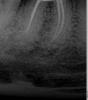

Jeanssp Опубликовано 1 октября, 2013 Поделиться Опубликовано 1 октября, 2013 Здравствуйте! более полугода лечил зуб, удаляли нерв. Зуб по утрам ноет, стал реагировать на температуру. Снимок прилагается. Что посоветуете ? Ссылка на комментарий

red_butler Опубликовано 1 октября, 2013 Поделиться Опубликовано 1 октября, 2013 Сделайте панорамный снимок и выкладывайте, а зуб перелечивайте Ссылка на комментарий